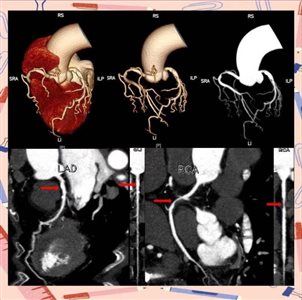

冠脉CT属于无创检查,通过静脉注射造影剂后进行CT扫描,清晰地显示冠状动脉的结构、斑块及狭窄程度。检查便捷、无需住院,门诊即可完成,风险较低,适合作为冠心病初步筛查手段。对于胸闷症状不典型、无明显高危因素、仅需体检排查或术前常规评估的人群,优先选择冠脉CT。但心率过快、严重钙化会影响成像精度,且无法同步进行治疗。